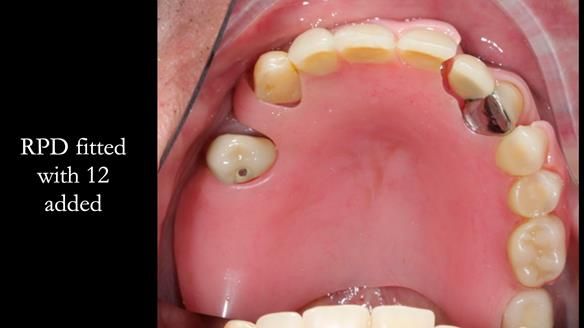

This edition features the case of Edgar, who sought help for a poorly fitting, acrylic-based partial denture that rocked, affected his speech, and caused discomfort. After considering various treatment options, including dental implants, Edgar opted for a metal-based removable partial denture, designed by myself with input from my technician, Rowan Garstang.

Treatment Process: I provided the clinical work while Rowan Garstang delivered the technical aspects. The treatment required fifteen visits to fit and review Edgar.